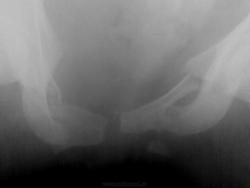

Случай 2.

Мужчина. ДТП, этим все сказано....ну и - всего много...

2. Оскольчатая бабочка + разрыв симфиза. С левой подвздошной в крыле - не совсем уверена. Удивительно, что мочевой цел... или ошибаюсь?

2. И крыло подвздошной, и левая половина крестца, и поперечный пятого поясничного - все так и есть... Да, на удивление, мочевой "удержал")))

А по крестцу - каша, не понять... Поперечный 4-го отлетел слева, а в поперечном 5-м видится асимметричная сакрализация. Крыло погнуто наверняка, но деталей не могу рассмотреть, наощупь всё). Мочевой - молодец, железный мочевой)).

А во втором случае - таз всмятку!

Случай №2. Перелом крестцовоподвздошного сочленения слева со смещением подвздошной кости. Двусторонний перелом лонных и седалищных костей, разрыв лонного сочленения.